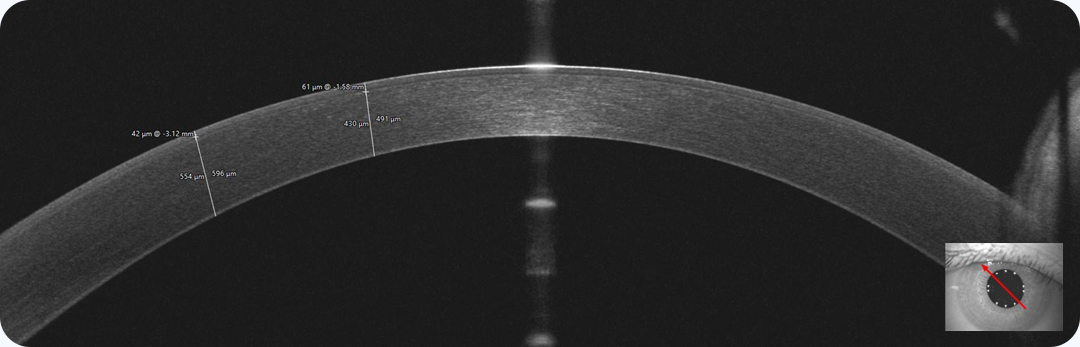

최상위 아마리스, 아마리스 레드는 그 자체로도 훌륭하지만

MS-39로 인해 더욱 완벽해집니다